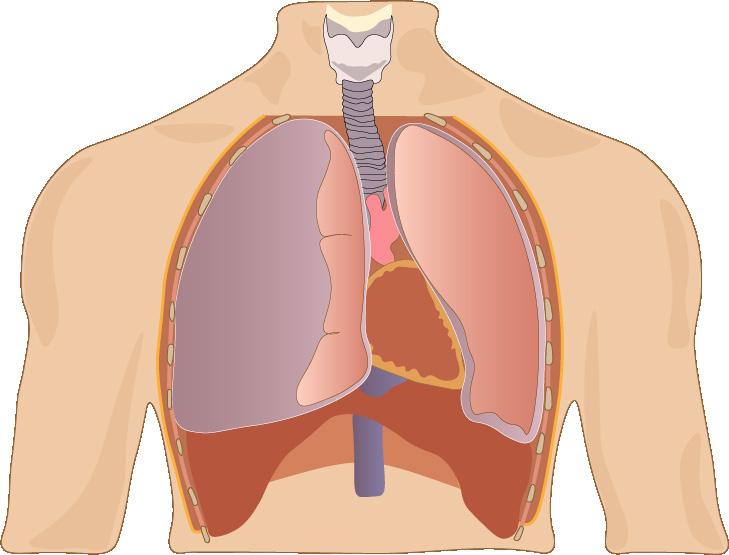

Figura 9. Hemotórax por acumulo de sangre en espacio pleural por laceración pulmonar Figura 10. Hemotórax → aumento de radiopacidad en hemitórax izquierdo Figura 11. La radiografía de tórax en posición vertical muestra una combinación de hemoneumotórax (flechas gruesas y delgadas, respectivamente). Figura 12. TAC tórax → ↑sensibilidad y especificidad para diagnóstico de hemotórax como se muestra en la imagen en lado izquierdo